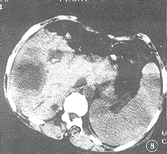

(3)CT檢查更能了解膿腔及病變的細微改變。

本病是結核性膿胸常見的併發症。結核性膿胸的壁層胸膜破裂,自發排出其內容物,可進入許多部位,最常見的是胸壁皮下組織。CT 可同時顯示胸腔內外的病變,均呈厚壁的包裹性積液,且可顯示兩者之間的瘺。

結核性膿胸並發胸膜惡性腫瘤相對罕見,雖然其發病機理不明,但慢性炎症是最重要的因素,其病理學類型較多。診斷也相對較難。如出現以下徵象可提示本併發症: (1) 胸腔密度增高; (2) 胸壁軟組織腫脹,脂肪線模糊,或兩者同時出現; (3) 膿胸附近有骨質破壞; (4) 鈣化的胸膜廣泛內移; (5) 膿胸的腔內新發生氣液平面。此時應行CT 檢查,可發現膿胸周圍有軟組織密度腫物,增強掃描有強化。在診斷中應注意胸膜腫瘤與自潰性膿胸的鑑別,腫瘤常有壞死或退行性囊變,但CT 值可與膿胸相似,重要的是發現軟組織腫塊的外形,其壁的厚度不規則和腔內有軟組織密度凸出影,可提示胸膜惡性腫瘤 。有時CT 對胸膜惡性腫瘤亦難以作出明確診斷,但能提供活檢的部位。